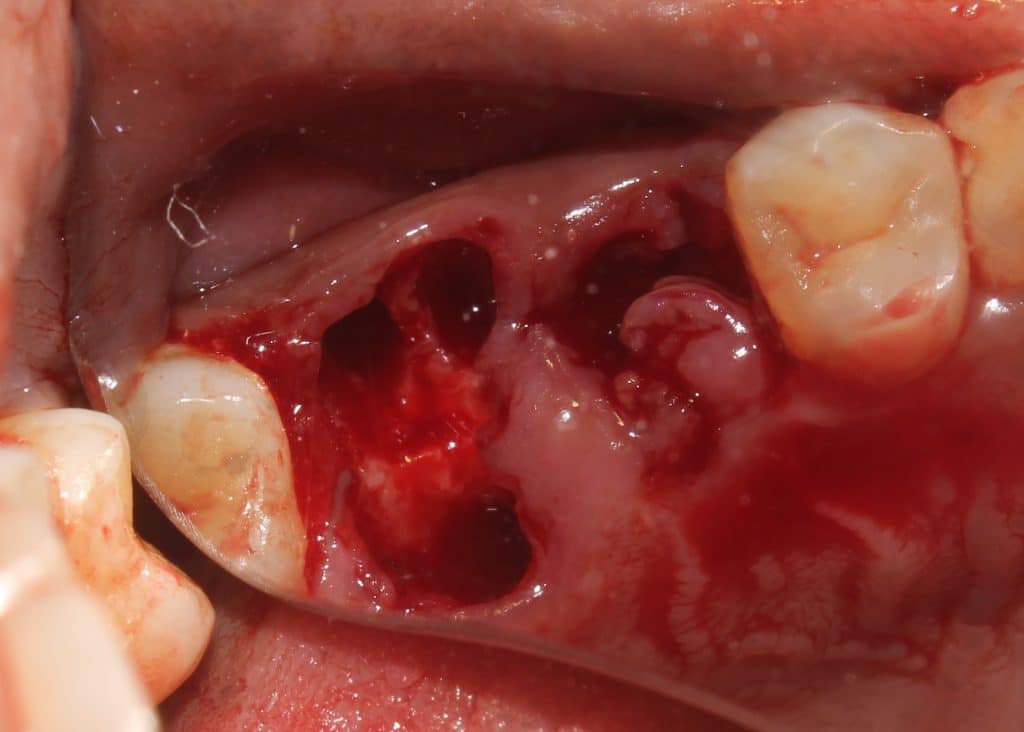

Initial presentation of broken down teeth.. previously root treated..

the premolar is elevated from the mesial purchase point.. and removed..

the distal and palatal roots are joined... so sectioning is done..

elevation and root forceps used to remove the distal root..

same is followed for mesial root..

followed by palatal root..

final photograph shows good preservation of furcal bone and buccal plate..

removed root stumps..